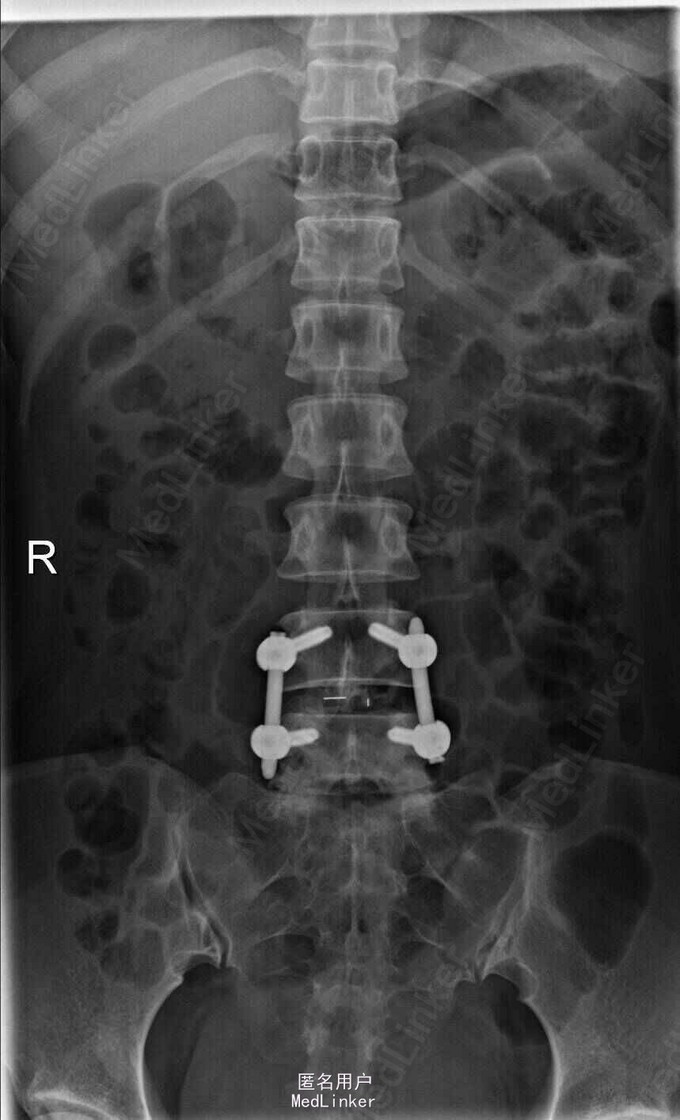

主诉:左下肢疼痛伴腰痛1月 病史:患者女性,39岁,十月前无明显原因发生腰痛,休息后缓解。未做其他治疗,1月前,出现左腿放射性疼痛,外侧及足后为主,腰部酸胀,无麻木等异常感,腰部活动障碍,不能正常行走,发病来大小便正常。在外院行ct检查后,诊断为腰椎间盘突出,未见影像片。

查体:脊柱无侧弯,腰部叩痛,活动障碍。上肢肌力感觉均正常。左下肢疼痛伴稍麻木感,肌力可,跟膝腱反射正常,直腿抬高试验:左侧55度,右侧35度,病理征未引出。 辅助检查:x线见腰椎退行性改变 MRI:L4-5,L5-S1椎间盘突出

诊断:L4-5,L5-S1椎间盘突出 治疗;患者神经压迫症状是由L4-5节段椎间盘突出所致,手术主要对L4-5节段减压,后固定。

随访:术后患者疼痛症状减轻,术后3月活动可。